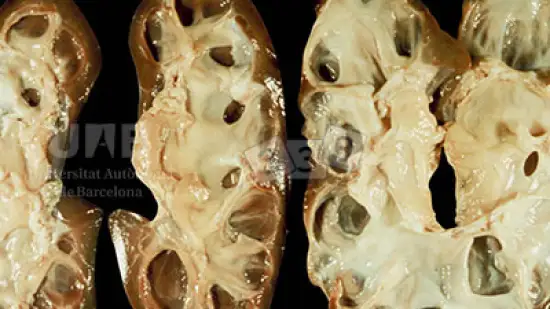

Qual è la causa più probabile degli ascessi nel prosciutto?